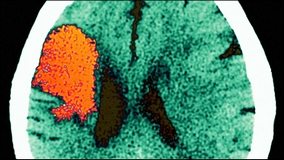

Atriyal fibrilasyon görülen hastalara doğru tedavi ne kadar erken verilirse, inme gibi ciddi sekonder etkilerin riski o kadar azaltılabiliyor. İsveç Gothenburg Üniversitesinde sunulan bir tez, iyi hesaplanmış ölçüm skoru ile bu hasta grubundaki kişilerin risklerinin kolayca değerlendirilebileceğini gösteriyor.

Uzun süreli atriyal fibrilasyon, kalp fonksiyonunu etkiler. Kalp daha zor yeniden yapılanır ve normal kalp ritmini daha geç yakalar. Bu da, tedaviyi güçleştirir ve ciddi sekonder etkilere neden olabilir. Uzmanlar, CHADS2 skoru olarak bilinen skorun, akut koroner sendromlu hastalarda atriyal fibrilasyon olsun veya olmasın, inme ile etkilenen risk ile ilişkili olup olmadığını araştırdı. CHADS2 skoru, atriyal fibrilasyonlu hastalarda inme riskinin değerlendirilmesinde kullanılır ve konjestif kalp yetmezliği, hipertansiyon (yüksek kan basıncı), ≥75 yaş, diyabet ve geçirilmiş inme varlığına dayanır.

Uzun süreli atriyal fibrilasyon, kalp fonksiyonunu etkiler. Kalp daha zor yeniden yapılanır ve normal kalp ritmini daha geç yakalar. Bu da, tedaviyi güçleştirir ve ciddi sekonder etkilere neden olabilir. Uzmanlar, CHADS2 skoru olarak bilinen skorun, akut koroner sendromlu hastalarda atriyal fibrilasyon olsun veya olmasın, inme ile etkilenen risk ile ilişkili olup olmadığını araştırdı. CHADS2 skoru, atriyal fibrilasyonlu hastalarda inme riskinin değerlendirilmesinde kullanılır ve konjestif kalp yetmezliği, hipertansiyon (yüksek kan basıncı), ≥75 yaş, diyabet ve geçirilmiş inme varlığına dayanır.

Dritan Poçi, uzun süreli takip döneminde yüksek CHADS2 skorunun, yüksek inme riski ve erken (30 gün) veya geç ölüm olayları ile ilişkili olduğunu belirtiyor ve ekliyor: “Çalışmamızda bu skorun iyi hesaplandığını ve atriyal fibrilasyon olmayan ancak akut koroner sendromu olan hastalarda bile elde edilen sonuçlar ile ilişkili olduğunu gördük. Bu da, CHADS2 skorunun yüksek müteakip inme ve ölüm riski olan hastaları belirlemede kullanılabileceği anlamına geliyor.”

Dr. Poçi, daha önce atriyal fibrilasyon olduğu bilinen ve yeni tanı konan hastalar için bu tür bir risk değerlendirmesinin yapılması gerektiğini düşünüyor. Hatta bu değerlendirme, atriyal fibrilasyondan bağımsız olarak, miyokard infarktüsüne ilişkin semptomları olan hastalarda da yapılabilir.